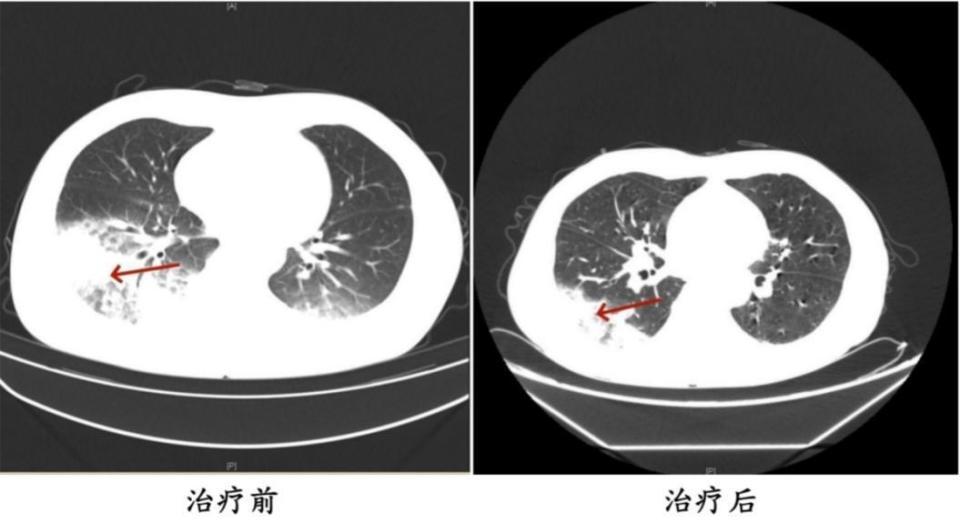

入院后,呼吸与危重症医学科副主任、副主任医师刘达详细询问患者病史,得知姚女士既往有2型糖尿病、甲状腺恶性肿瘤(乳头状癌术后)、甲状腺功能减退、特纳综合征等病史,是免疫力低下人群。再结合体格检查及相关辅助检查结果,初步判断患者为重症社区获得性肺炎。经抗感染治疗后,患者的病情逐渐加重,反复高热,出现多脏器功能异常,如心肌酶谱异常升高、低钠血症、血尿、蛋白尿等状况。刘达及团队通过分析患者咳出橘红色痰以及肺内、肺外表现,建议完善病原学检查,最终确诊为重症军团菌肺炎。调整用药后,患者病情迅速好转,体温逐渐恢复正常,各项指标逐步恢复。